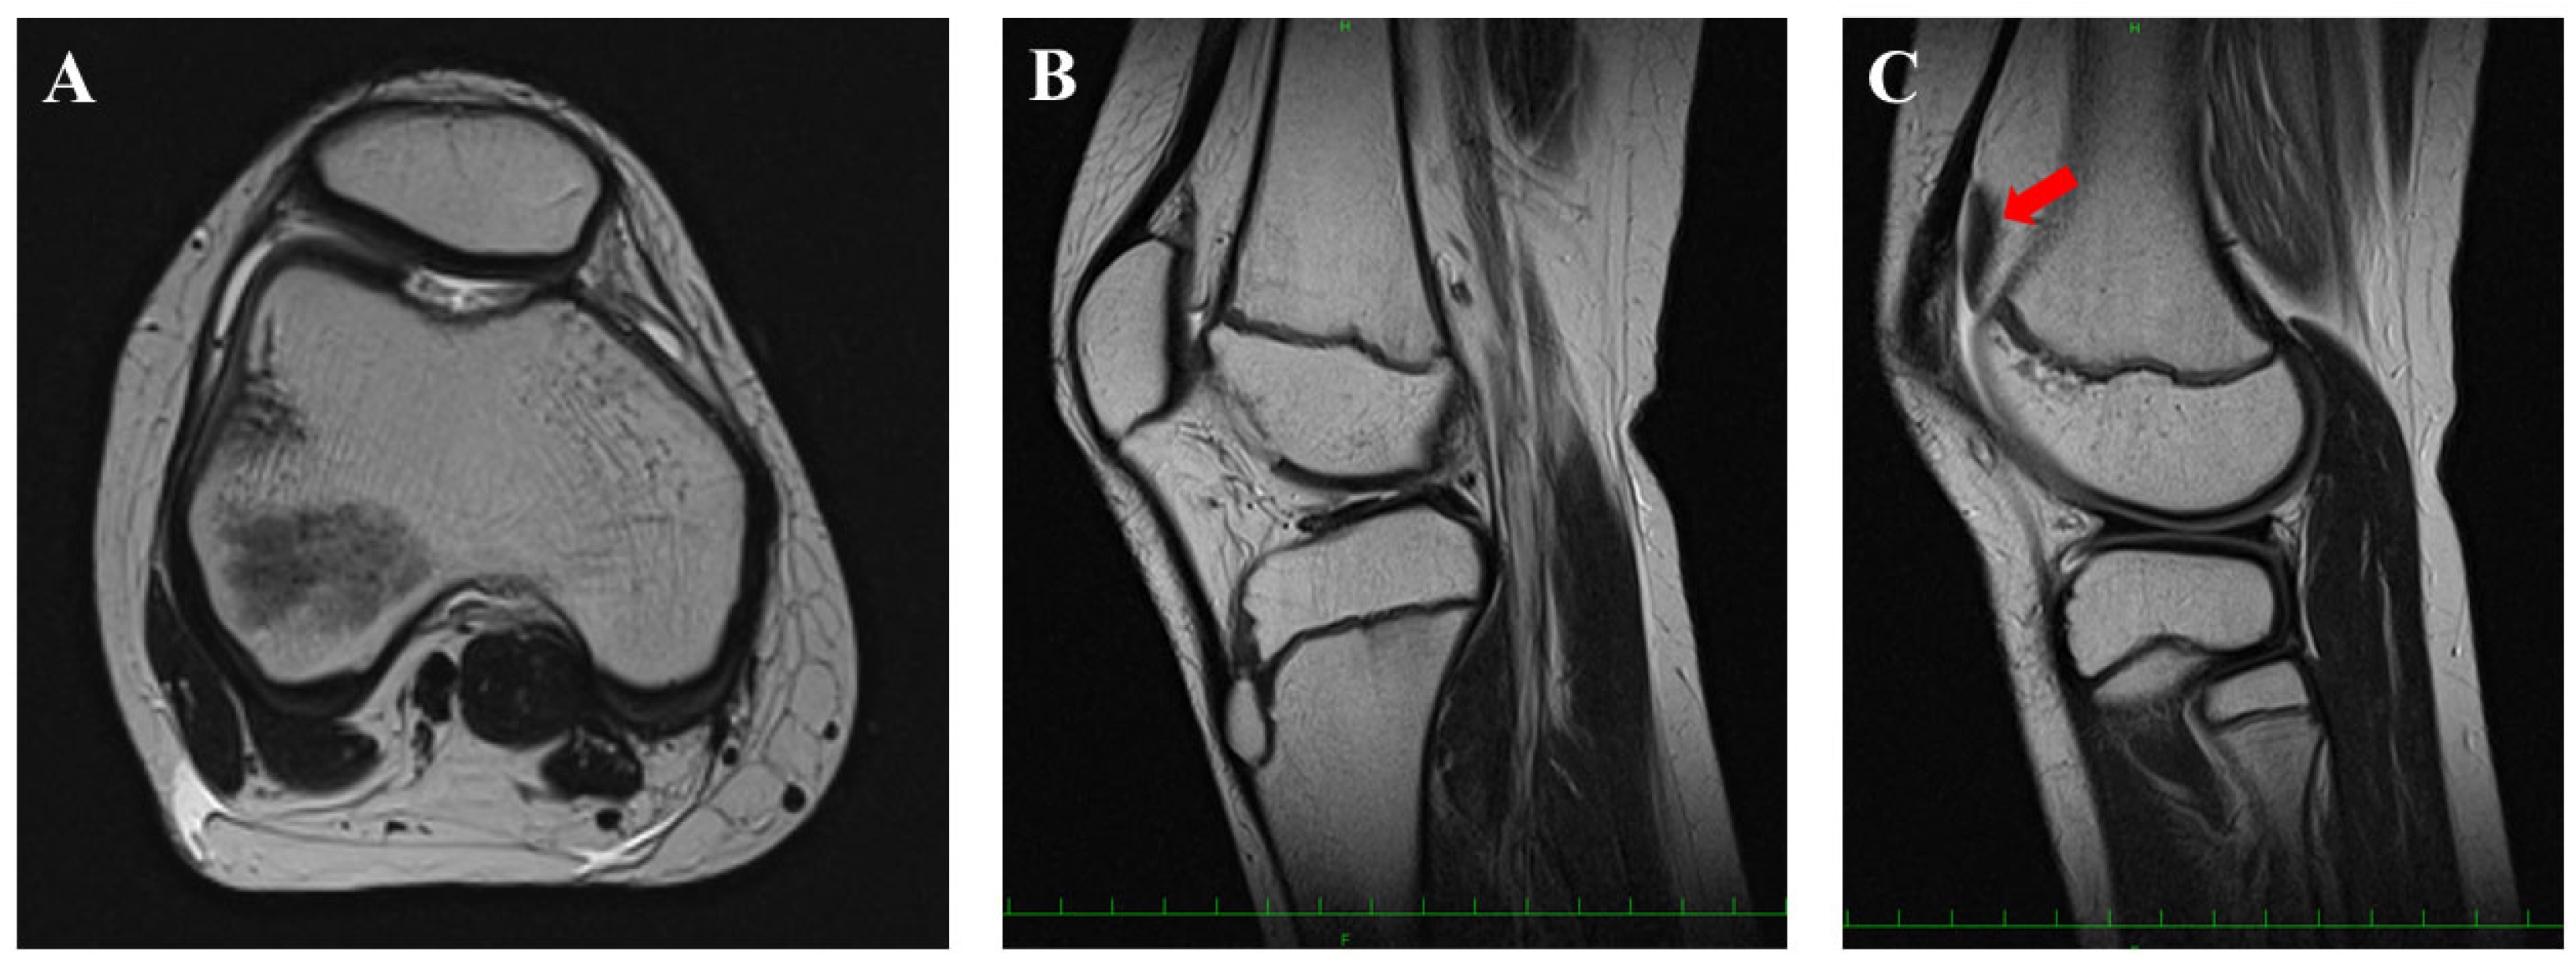

2. Case Presentation